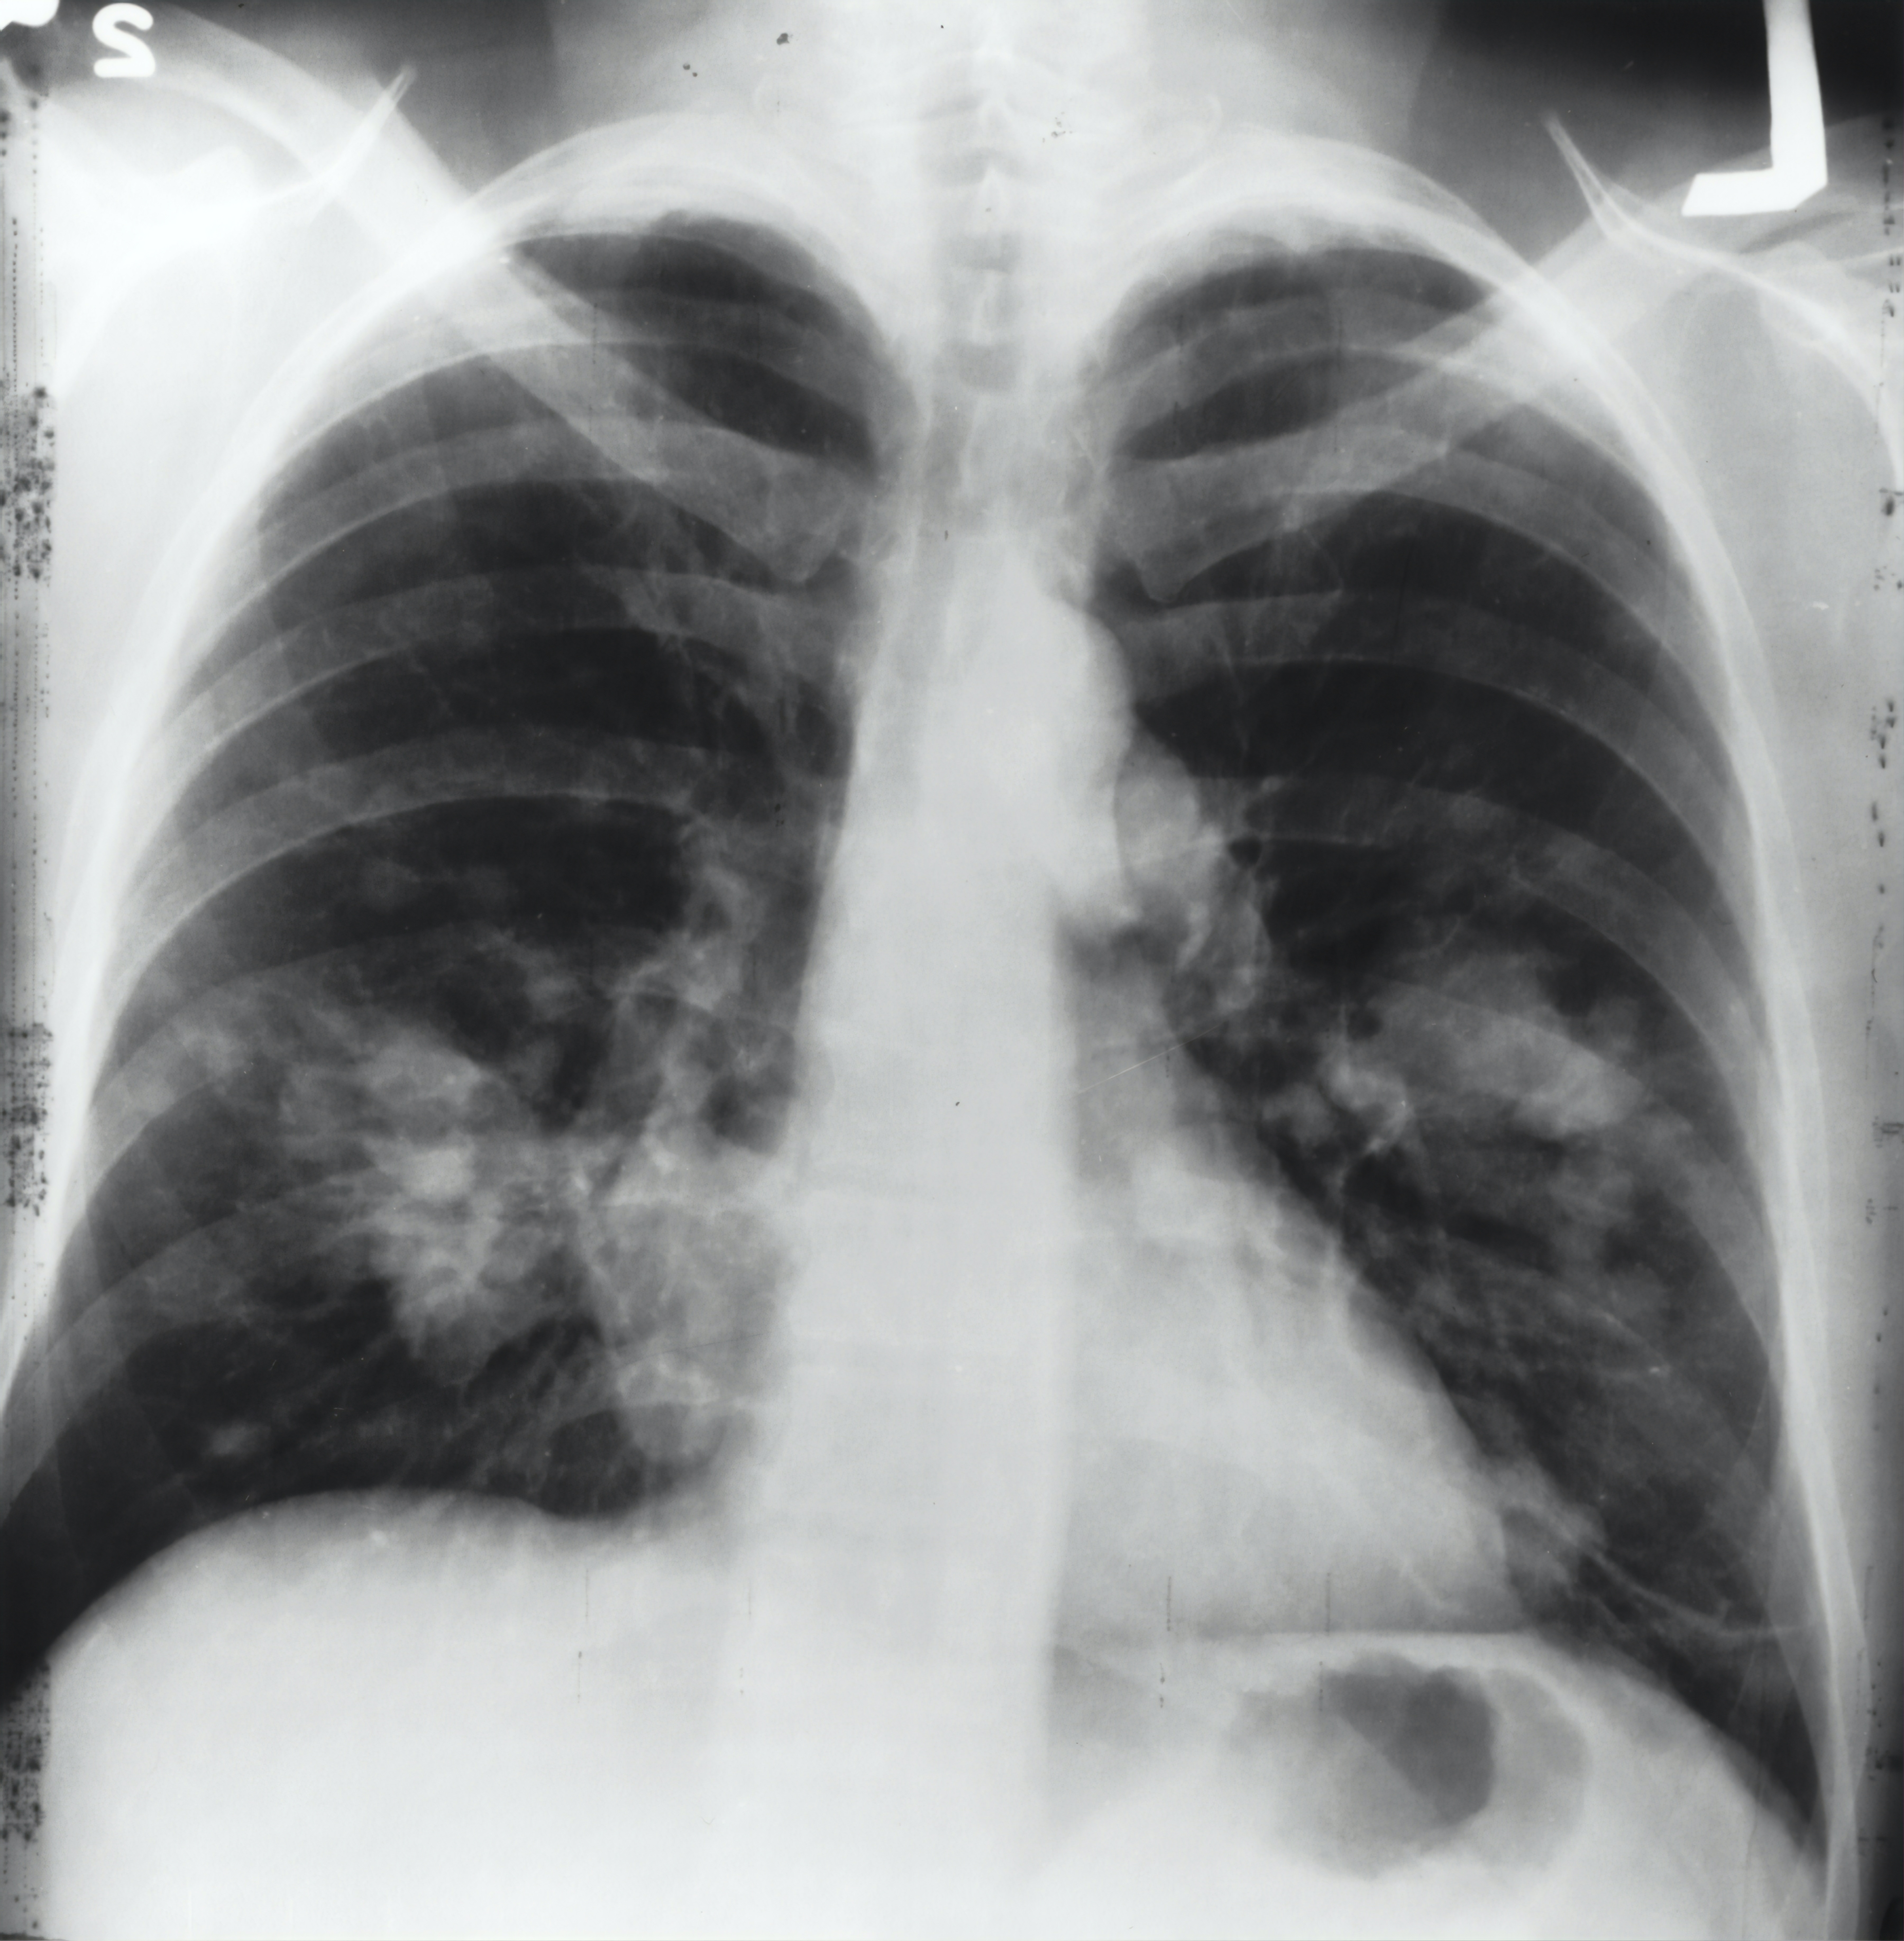

- 가슴 내장기 문제: 심장, 폐, 간, 췌장 등 가슴 내장기에 문제가 있을 때 갈비뼈 주위로 통증이 느껴질 수 있습니다.